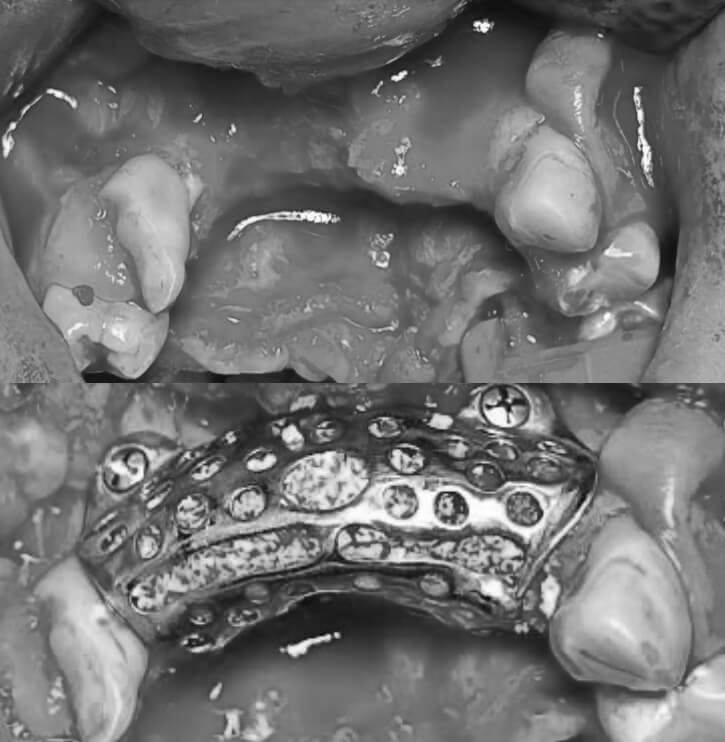

- Ivan is 23 years old and originally wanted to become an engineer. But in 2022, he volunteered to defend Ukraine. A mine explosion destroyed parts of his face. Surgeons were able to reconstruct his upper jaw using a 3D implant.